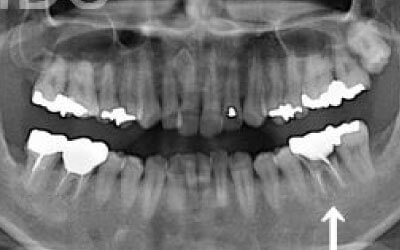

3 歯周病でインプラントが抜けるリスク

細菌(歯垢)によって、インプラントを支える歯茎や骨が徐々に減少することがあります。

ですので、インプラント治療だけでなく、残っている歯の歯周病のチェックや治療も非常に重要です。